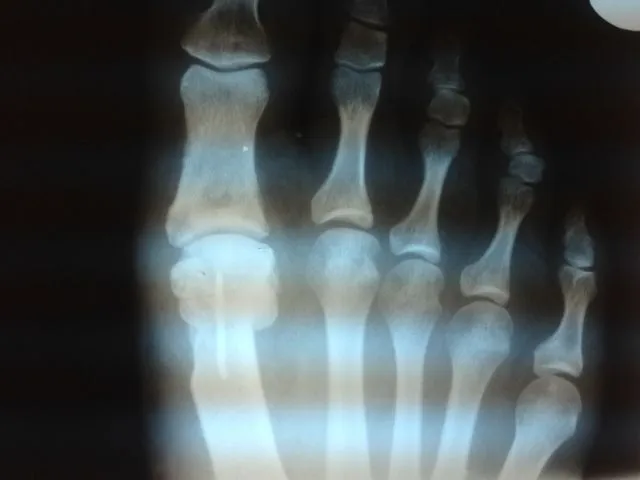

Before and immediately postop S/P bunionectomy

Before and 6 months status post bunionectomy.

Pre and Postop Xrays